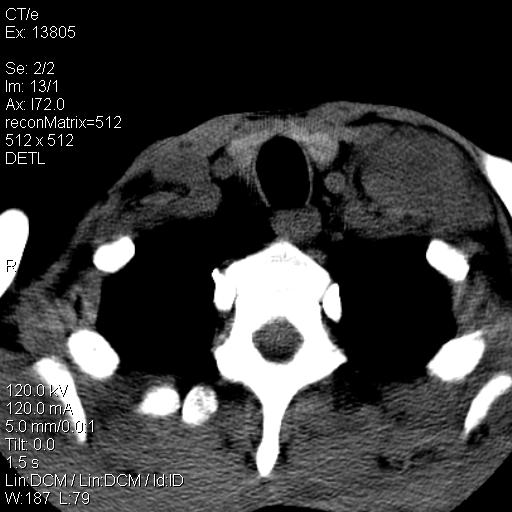

上腹部疼痛一月,呕吐10天,发现左侧颈部包快10天 胸部cr片未见明显异常。

左侧胸锁乳突肌下方、颈血管旁低密度肿块影,肿块密度尚均匀,边缘大部分清楚,邻近组织稍受压移位。考虑颈部神经鞘瘤可能性大。